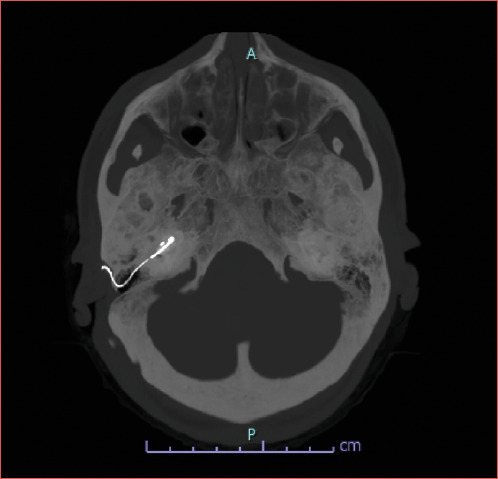

Objective: Management of advanced otosclerosis (AO) has evolved over the past 20 years with the availability of cochlear implant (CI) in addition to stapes surgery. Both procedures are reliable treatment options for AO with similar success rates and currently there are no standard guidelines regarding the surgical treatment of AO. The aim of this paper is to report the outcomes and complications of a series of patients with AO submitted to CI at our Institution. An extensive review of the literature is also provided.

Methods: The study group was composed of 31 adult patients affected by AO, consecutively submitted to CI at our Institution. Postoperative results and complications were compared to those of a homogeneous control group of adult implanted patients, affected by post-verbal sensorineural hearing loss due to other aetiologies.

Results: Patients in both groups achieved satisfactory results in terms of speech perception in quiet and with background noise after CI, without no significant differences. The rate of complications in the study group was 15%, which is similar to literature reports.

Conclusions: In patients with AO, the decision between stapes surgery and CI must be personalised and well-considered, taking into account the individual characteristics of the patient and the potential risks and benefits of each option.